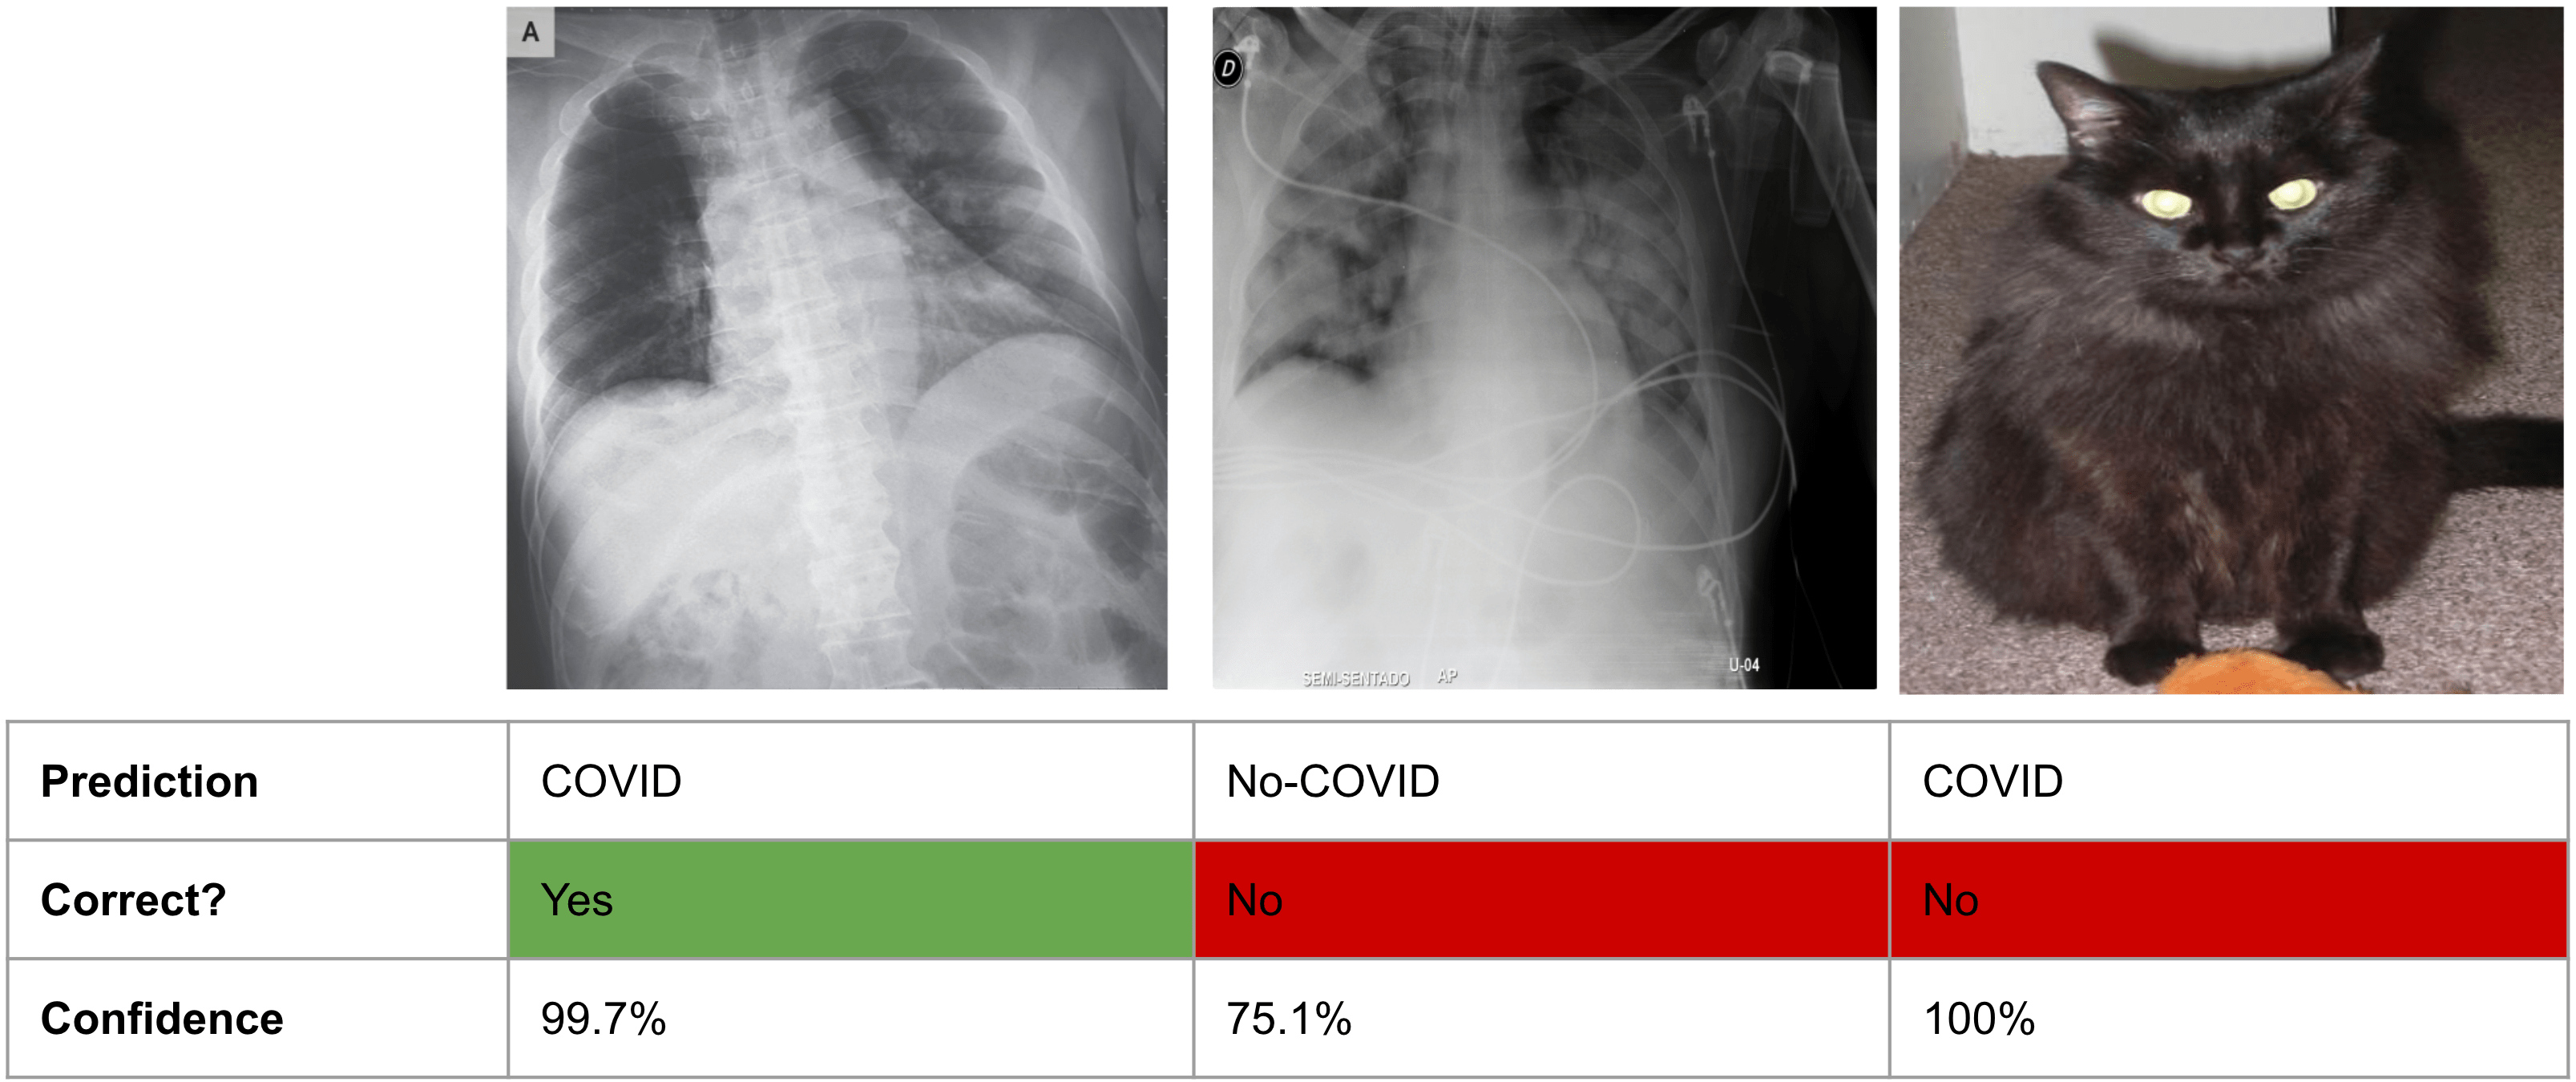

Especially in recent years, there has been more and more research dedicated to developing models that can reliably quantify uncertainty. As an example, a recent paper evaluated how confident different deep learning models are on a medical imaging task. In the paper, the authors evaluated models for predicting whether patients had COVID or not from X-ray scans. Here’s what they found:

Fig. 21.1 ML models can be over-confident about wrong predictions. Figure adapted from this paper.#

As you can see from the figure, the model makes predictions that aren’t only incorrect, but also overconfident. And it does this for inputs (like the cat) for which it should really just communicate “I don’t know.”